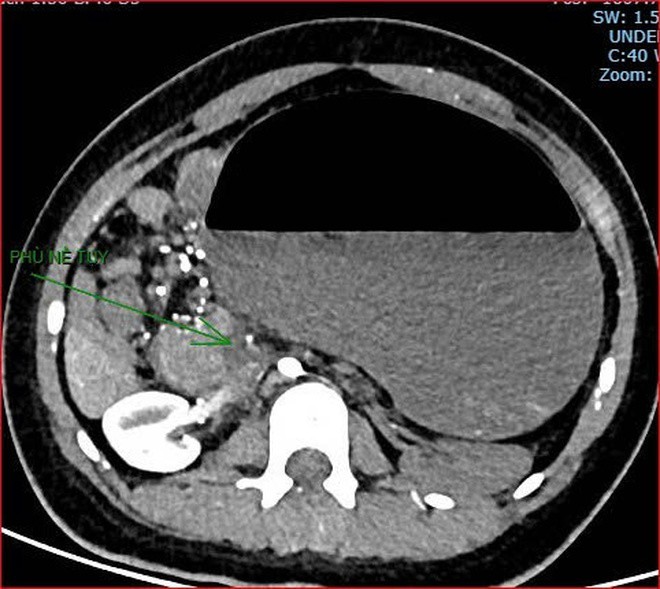

Khoảng 21 giờ 40, kết quả chụp CT cho thấy bệnh nhân rơi vào tình trạng cực kỳ nặng và hiếm gặp, bao gồm: xoắn dạ dày, nhồi máu thận trái, nhồi máu lách, viêm đầu tụy, viêm hỗng tràng, kèm dịch ổ bụng và tràn dịch màng phổi, trên nền bệnh nhân mắc hội chứng Down và tim bẩm sinh.

Hình ảnh chụp CT ổ bụng cho thấy dạ dày giãn lớn, xoắn bất thường; kèm tổn thương nhồi máu lách và viêm tụy trên nền ca bệnh hiếm, diễn biến đặc biệt nặng - Ảnh Bệnh viện cung cấp

Hình ảnh chụp CT ổ bụng cho thấy dạ dày giãn lớn, xoắn bất thường; kèm tổn thương nhồi máu lách và viêm tụy trên nền ca bệnh hiếm, diễn biến đặc biệt nặng – Ảnh Bệnh viện cung cấp